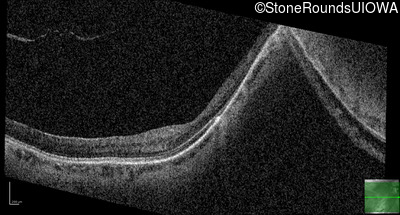

Age at visit: 41 years (Visit 2)

This 41 year old woman was highly myopic as a child and experienced a rhegmatogenous retinal detachment OS at age 20.

The clinical features favoring the diagnosis of Sticker syndrome in this patient include extensive radial lattice degeneration, a personal and family history of rhegmatogenous retinal detachment, a history of cataract surgery before age 30 (and very high myopia before that), arthritis in her knees and hips and a slightly flattened mid-face.